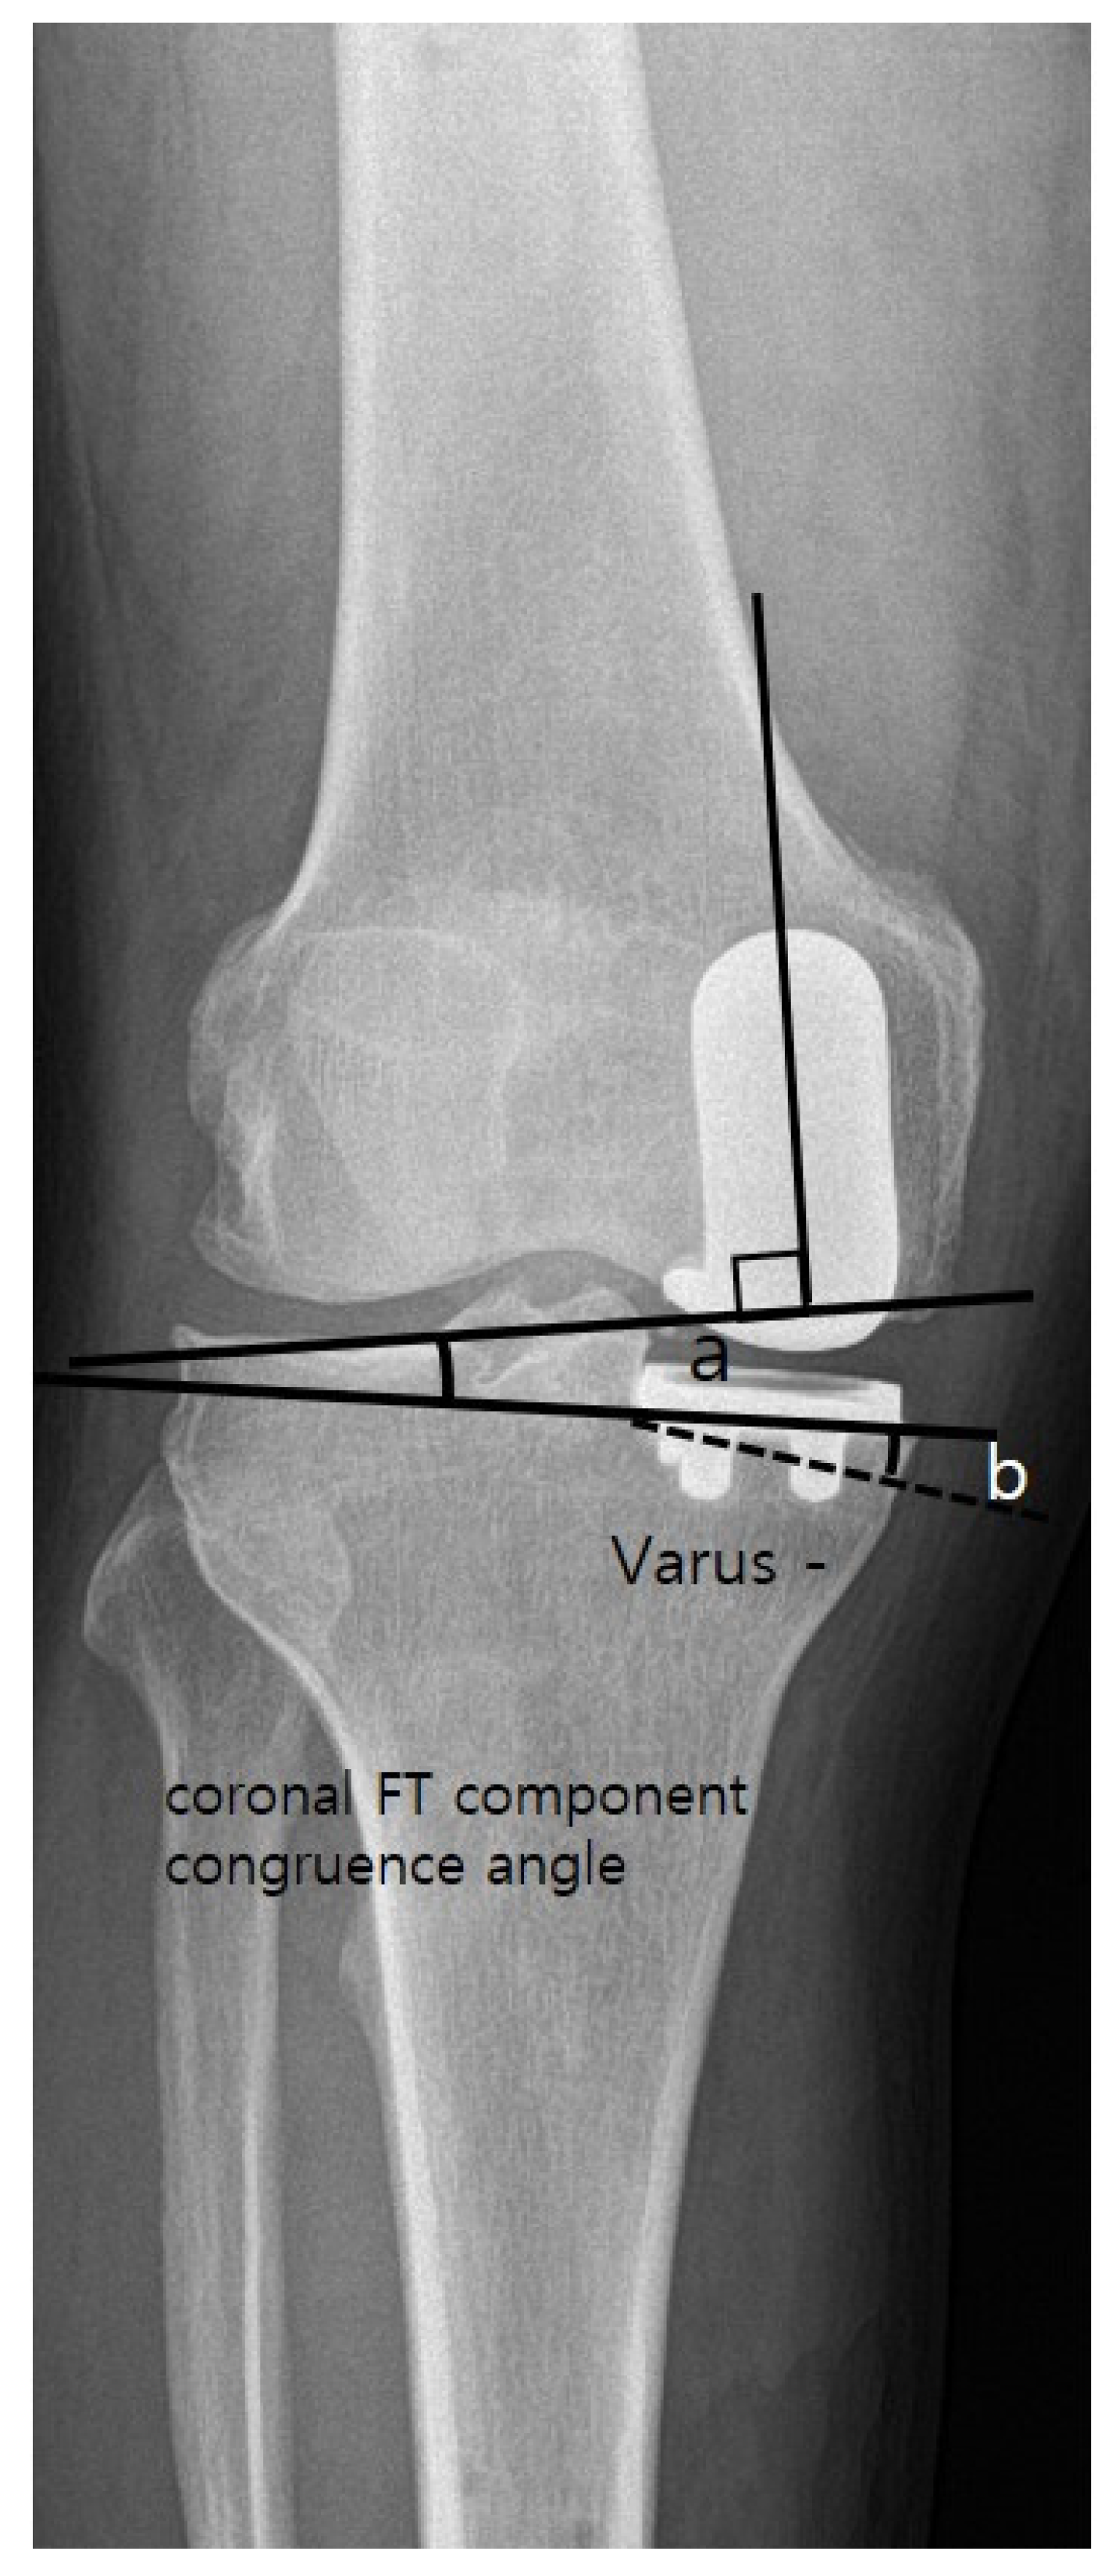

4. Clinical and Radiological Assessment

| Coronal FT component congruence angle (°) | 3.4 ± 4.5 | 1.9 ± 2.6 | 0.028 |

| Coronal tibial component angle (β) (°) | −1.0 ± 4.3 | −3.0 ± 2.4 | 0.001 |

| Coronal femoral component angle (α) (°) | 2.4 ± 4.9 | −1.1 ± 3.2 | <0.001 |